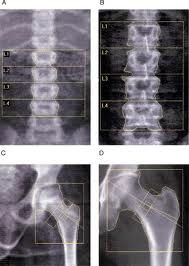

A bone density test uses X-rays to measure how many grams of calcium and other bone minerals are packed into a segment of bone. The bones that are most commonly tested are located in the spine, hip and forearm.

A DEXA bone densitometry test is most often used to aid in the diagnosis of osteoporosis and other conditions that cause bone loss. It is also a very useful tool for evaluating the effects that treatment has had on those conditions.